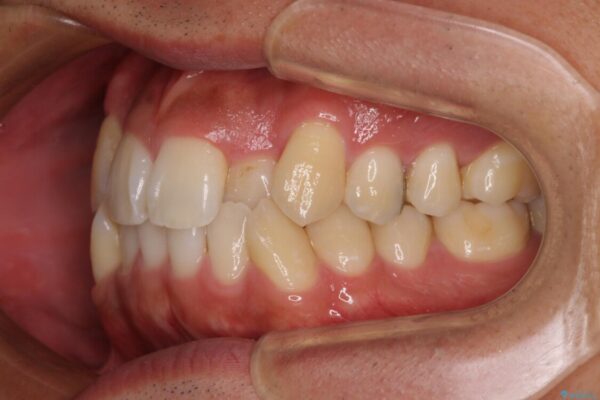

上下の前歯部に強い叢生(ガタガタの歯並び)があり、そのまま歯を並べると出っ歯になってしまう可能性がありました。

そこで、上下左右の第一小臼歯を抜歯し、歯が並ぶためのスペースを確保し叢生を解消する治療計画を立てました。

治療前

• 八重歯と前歯のガタガタを抜歯矯正で治療|クリアブラケット使用例 治療前画像